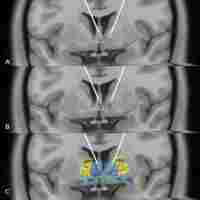

| Description | Abstract: Deep brain stimulation (DBS) is a neuro-psychosurgical technique widely accepted in movement disorders, such as Parkinson's disease. Since 1999, DBS has been explored for severe, chronic and treatment-refractory psychiatric diseases. Our review focuses on DBS in obsessive-compulsive disorder (OCD), considered as a last treatment resort by most of learned societies in psychiatry. Two main stimulation areas have been studied: the striatal region and the subthalamic nucleus. But, most of the trials are open-labeled, and the rare controlled ones have failed to highlight the most efficient target. The recent perspectives are otherwise encouraging. Indeed, clinicians are currently considering other promising targets. A case series of 2 patients reported a decrease in OCD symptoms after DBS in the medial forebrain bundle and an open-label study is exploring bilateral habenula stimulation. New response criteria are also investigating such as quality of life, or subjective and lived-experience. Moreover, first papers about cost-effectiveness which is an important criterion in decision making, have been published. The effectiveness of tractography-assisted DBS or micro-assisted DBS is studying with the aim to improve targeting precision. In addition, a trial involving rechargeable pacemakers is undergoing because this mechanism could be efficient and have a positive impact on cost-effectiveness. A recent trial has discussed the possibility of using combined cognitive behavioral therapy (CBT) and DBS as an augmentation strategy. Finally, based on RDoc Research, the latest hypotheses about the understanding of cortico-striato-thalamo-cortical circuits could offer new directions including clinical predictors and biomarkers to perform adaptive closed-loop systems in the next future. |